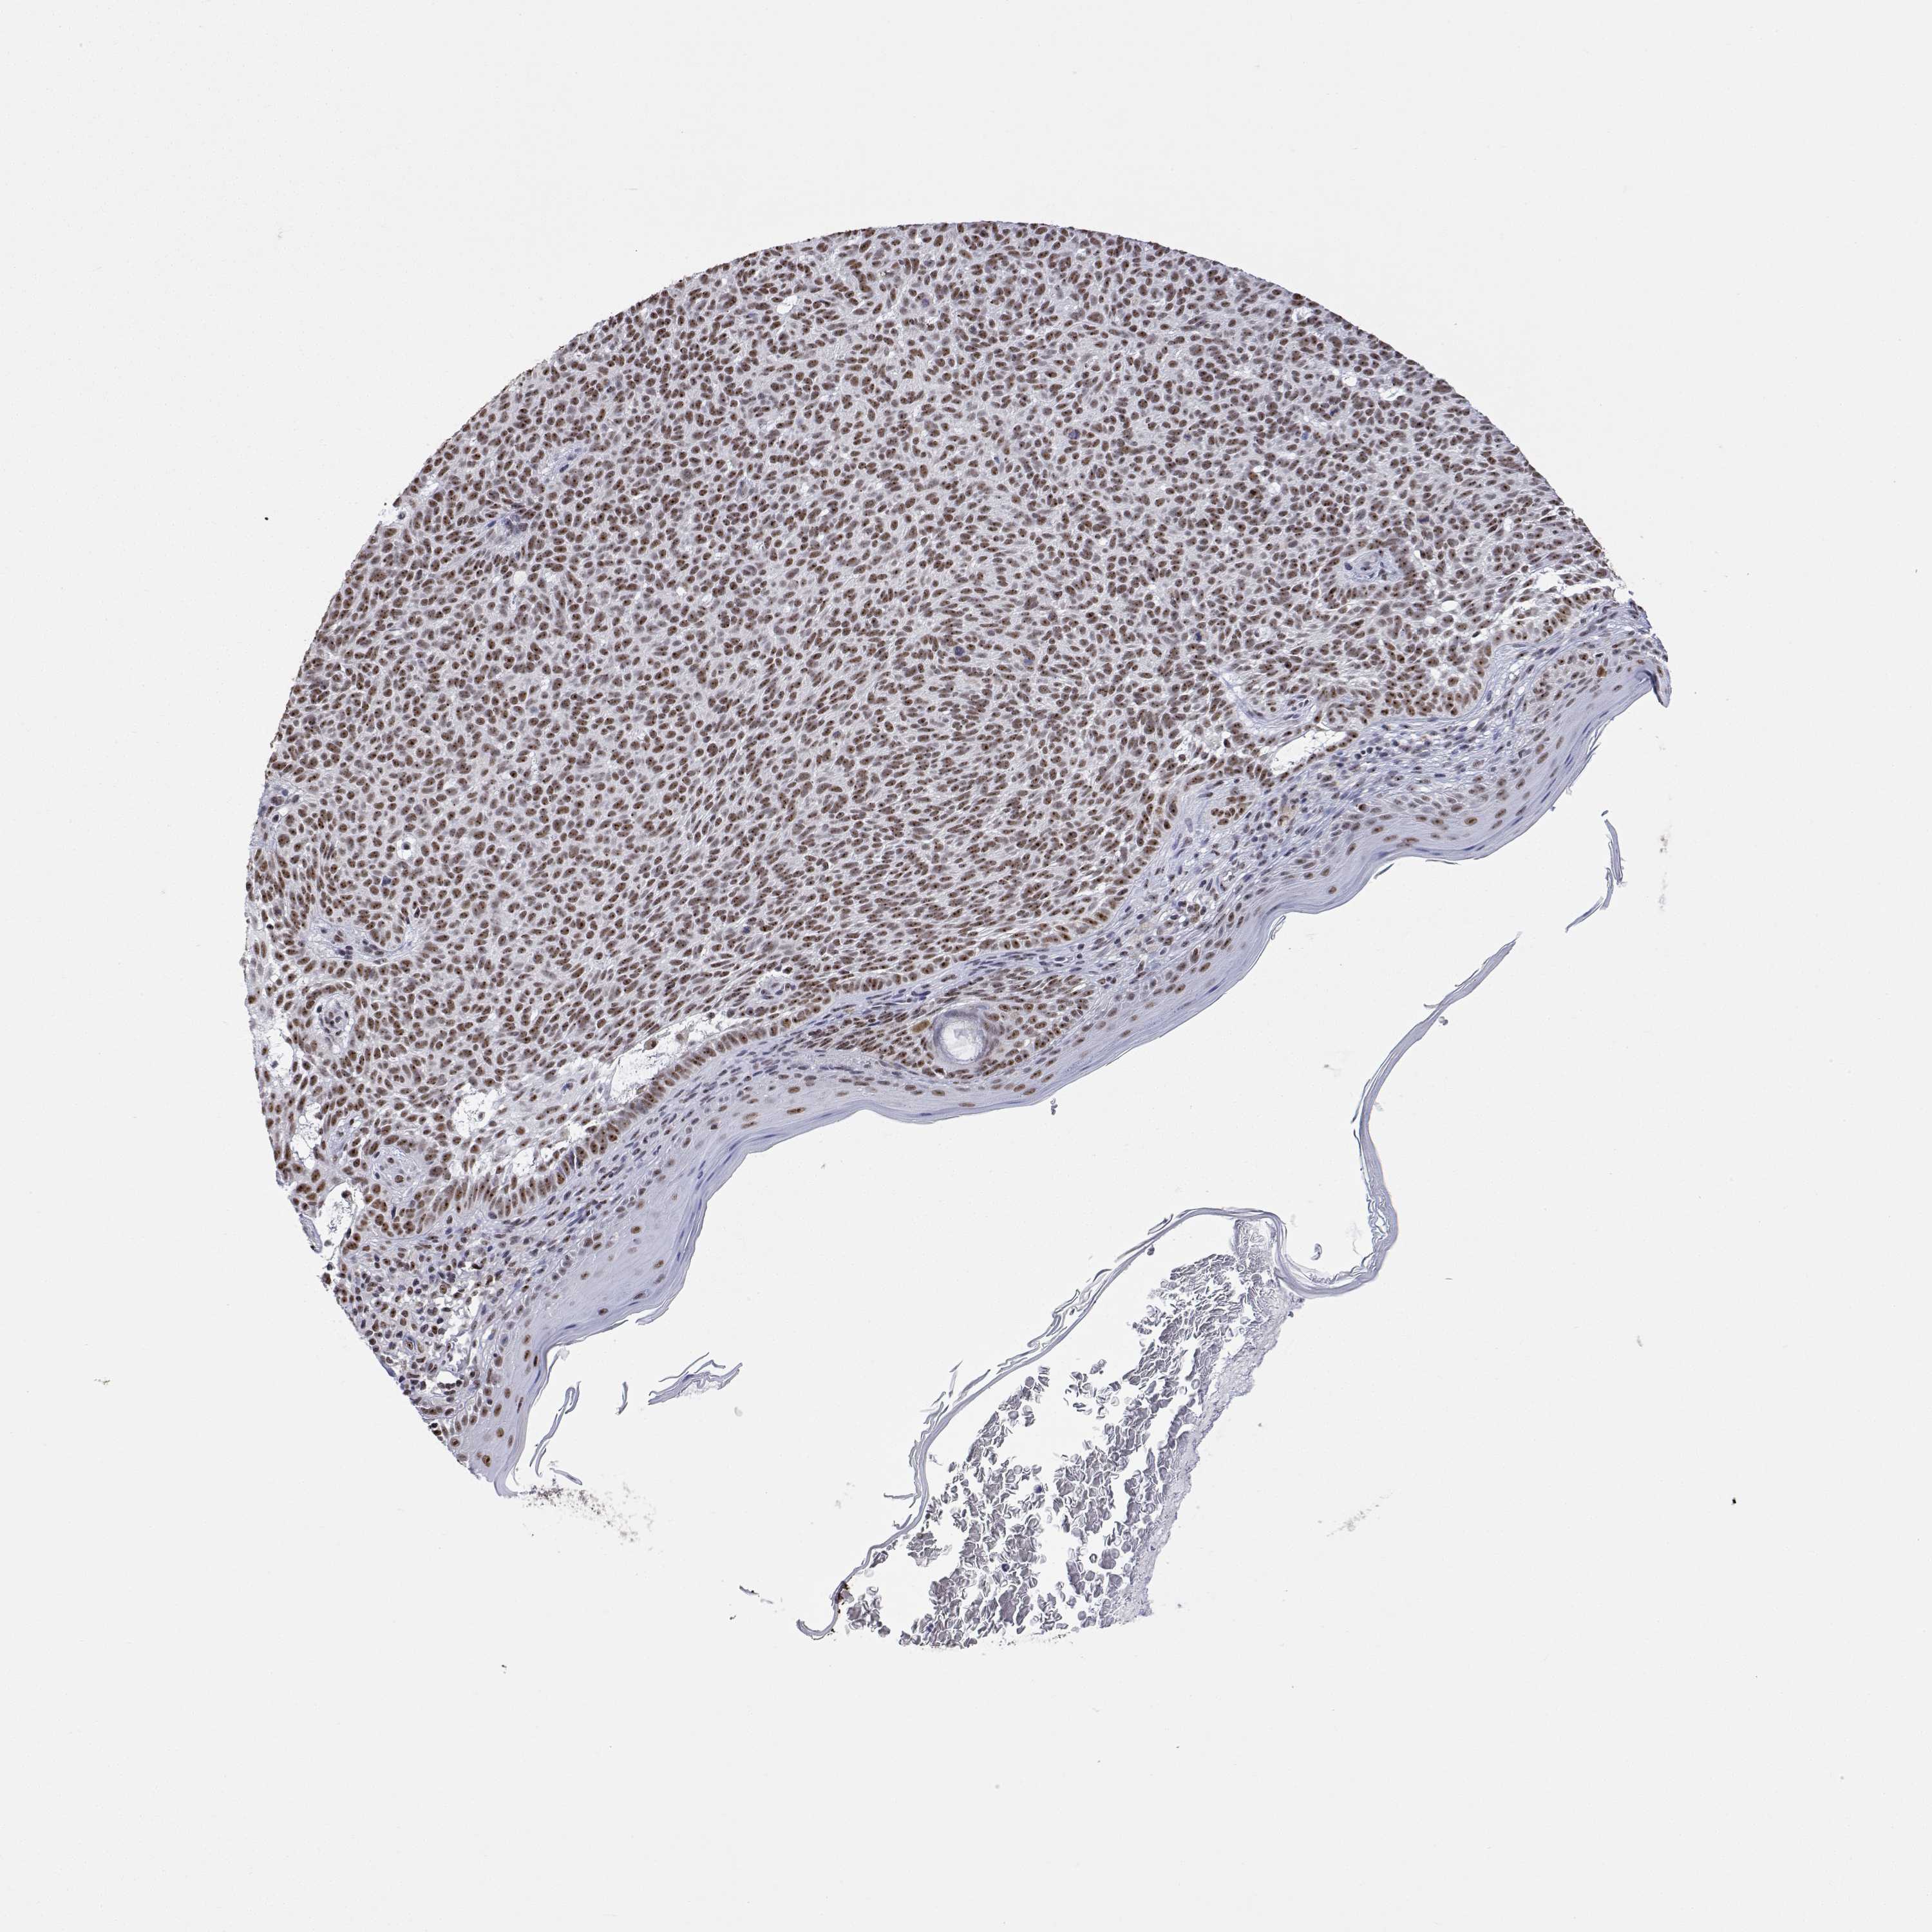

SKIN CANCER - Protein expressioni

A mouse-over function shows sample information and annotation data. Click on an image to view it in a full screen mode. Samples can be filtered based on level of antibody staining by selecting one or several of the following categories: high, medium, low and not detected. The assay and annotation is described here.

Each image is clickable and will lead to virtual microscopy that enables deeper exploration of all samples and also displays staining intensity scores, fraction scores and subcellular localization as well as patient and tissue information for each sample.

Antibody HPA051519

Staining

High

Medium

Low

Not detected

Intensity

Strong

Moderate

Weak

Negative

Quantity

>75%

75%-25%

<25%

None

Location

Nuclear

Cytoplasmic/membranous

Cytoplasmic/membranous,nuclear

Basal cell carcinoma

BCC, high aggressive